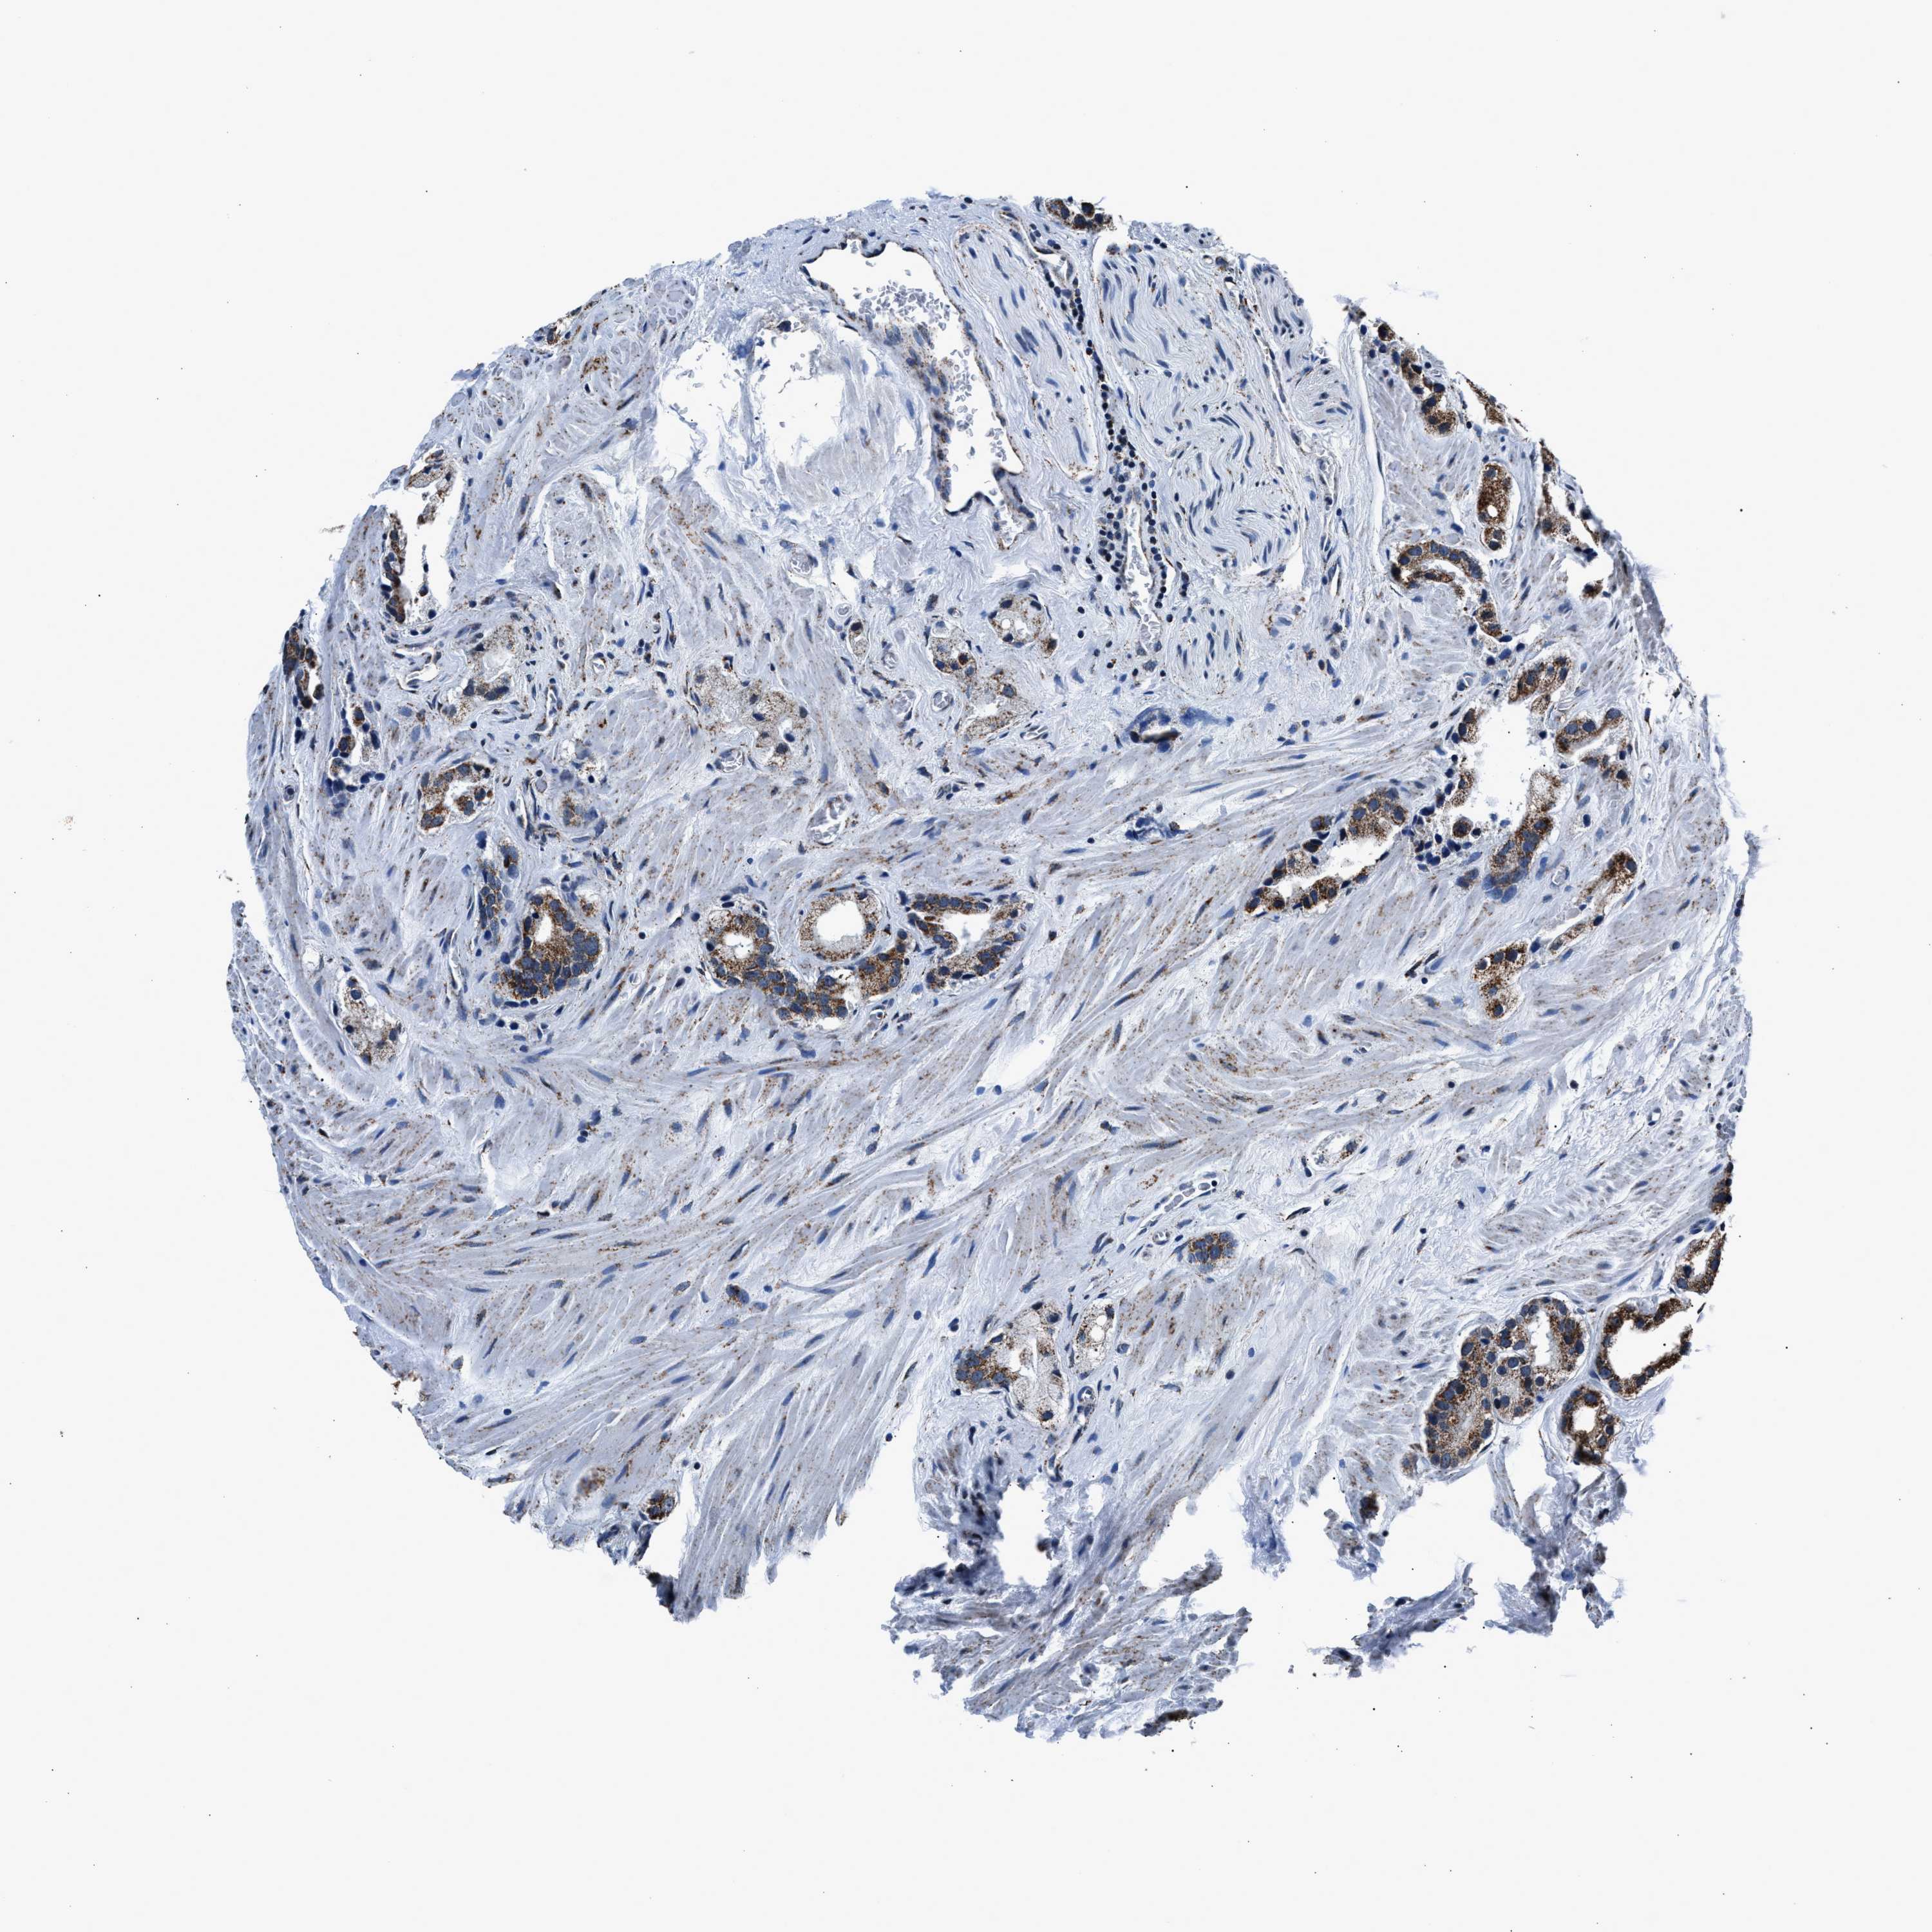

PROSTATE CANCER - Protein expressioni

A mouse-over function shows sample information and annotation data. Click on an image to view it in a full screen mode. Samples can be filtered based on level of antibody staining by selecting one or several of the following categories: high, medium, low and not detected. The assay and annotation is described here.

Antibody stainingi

Antibody staining in the annotated cell types in the current human tissue is reported as not detected, low, medium, or high, based on conventional immunohistochemistry profiling in selected tissues. This score is based on the combination of the staining intensity and fraction of stained cells.

Each image is clickable and will lead to virtual microscopy that enables deeper exploration of all samples and also displays staining intensity scores, fraction scores and subcellular localization as well as patient and tissue information for each sample.

Antibody HPA019522

Antibody HPA021002

Staining

High

Medium

Low

Not detected

Intensity

Strong

Moderate

Weak

Negative

Quantity

>75%

75%-25%

<25%

None

Location

Nuclear

Cytoplasmic/membranous

Cytoplasmic/membranous,nuclear

Adenocarcinoma, High grade

Adenocarcinoma, Low grade